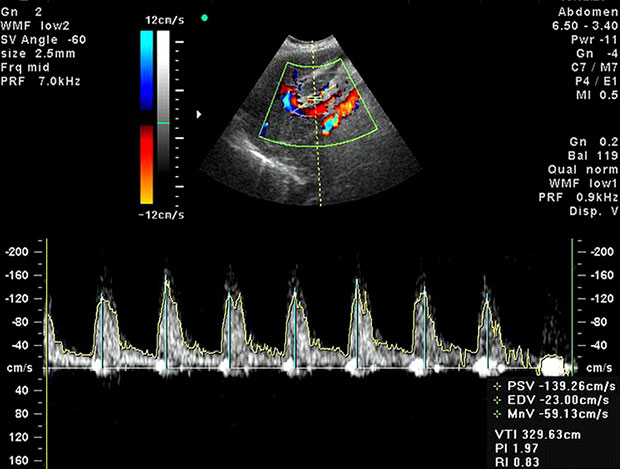

- дуплексное – с его помощью врач проверяет интенсивность кровотока и делает выводы относительно строения и проходимости сосудов;

- триплексное – показывает все то же самое, только в цветном изображении, благодаря чему специалист может проследить еще и движение эритроцитов и получить более развернутую картину протекания беременности.

Стоит отметить, что она проводится на современных модулях аппаратов ультразвукового исследования. При этом специалист получается целый ряд данных, анализируя которые он и может оценить кровоснабжение.